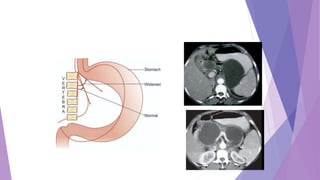

ULTRASOUND

Currently, CT is regarded as the

imaging modality of choice for the

initial evaluation of suggested

chronic pancreatitis.

The diagnostic features of:

• pancreatic ductal dilatation (68%)

• parenchymal atrophy (54%),

• pancreatic calcifications(50%)

• pancreatic enlargement

• thickening of the peripancreatic

fascia, and

• bile duct involvement

are depicted well on CT scans.

CT Findings

CT ABDOMEN